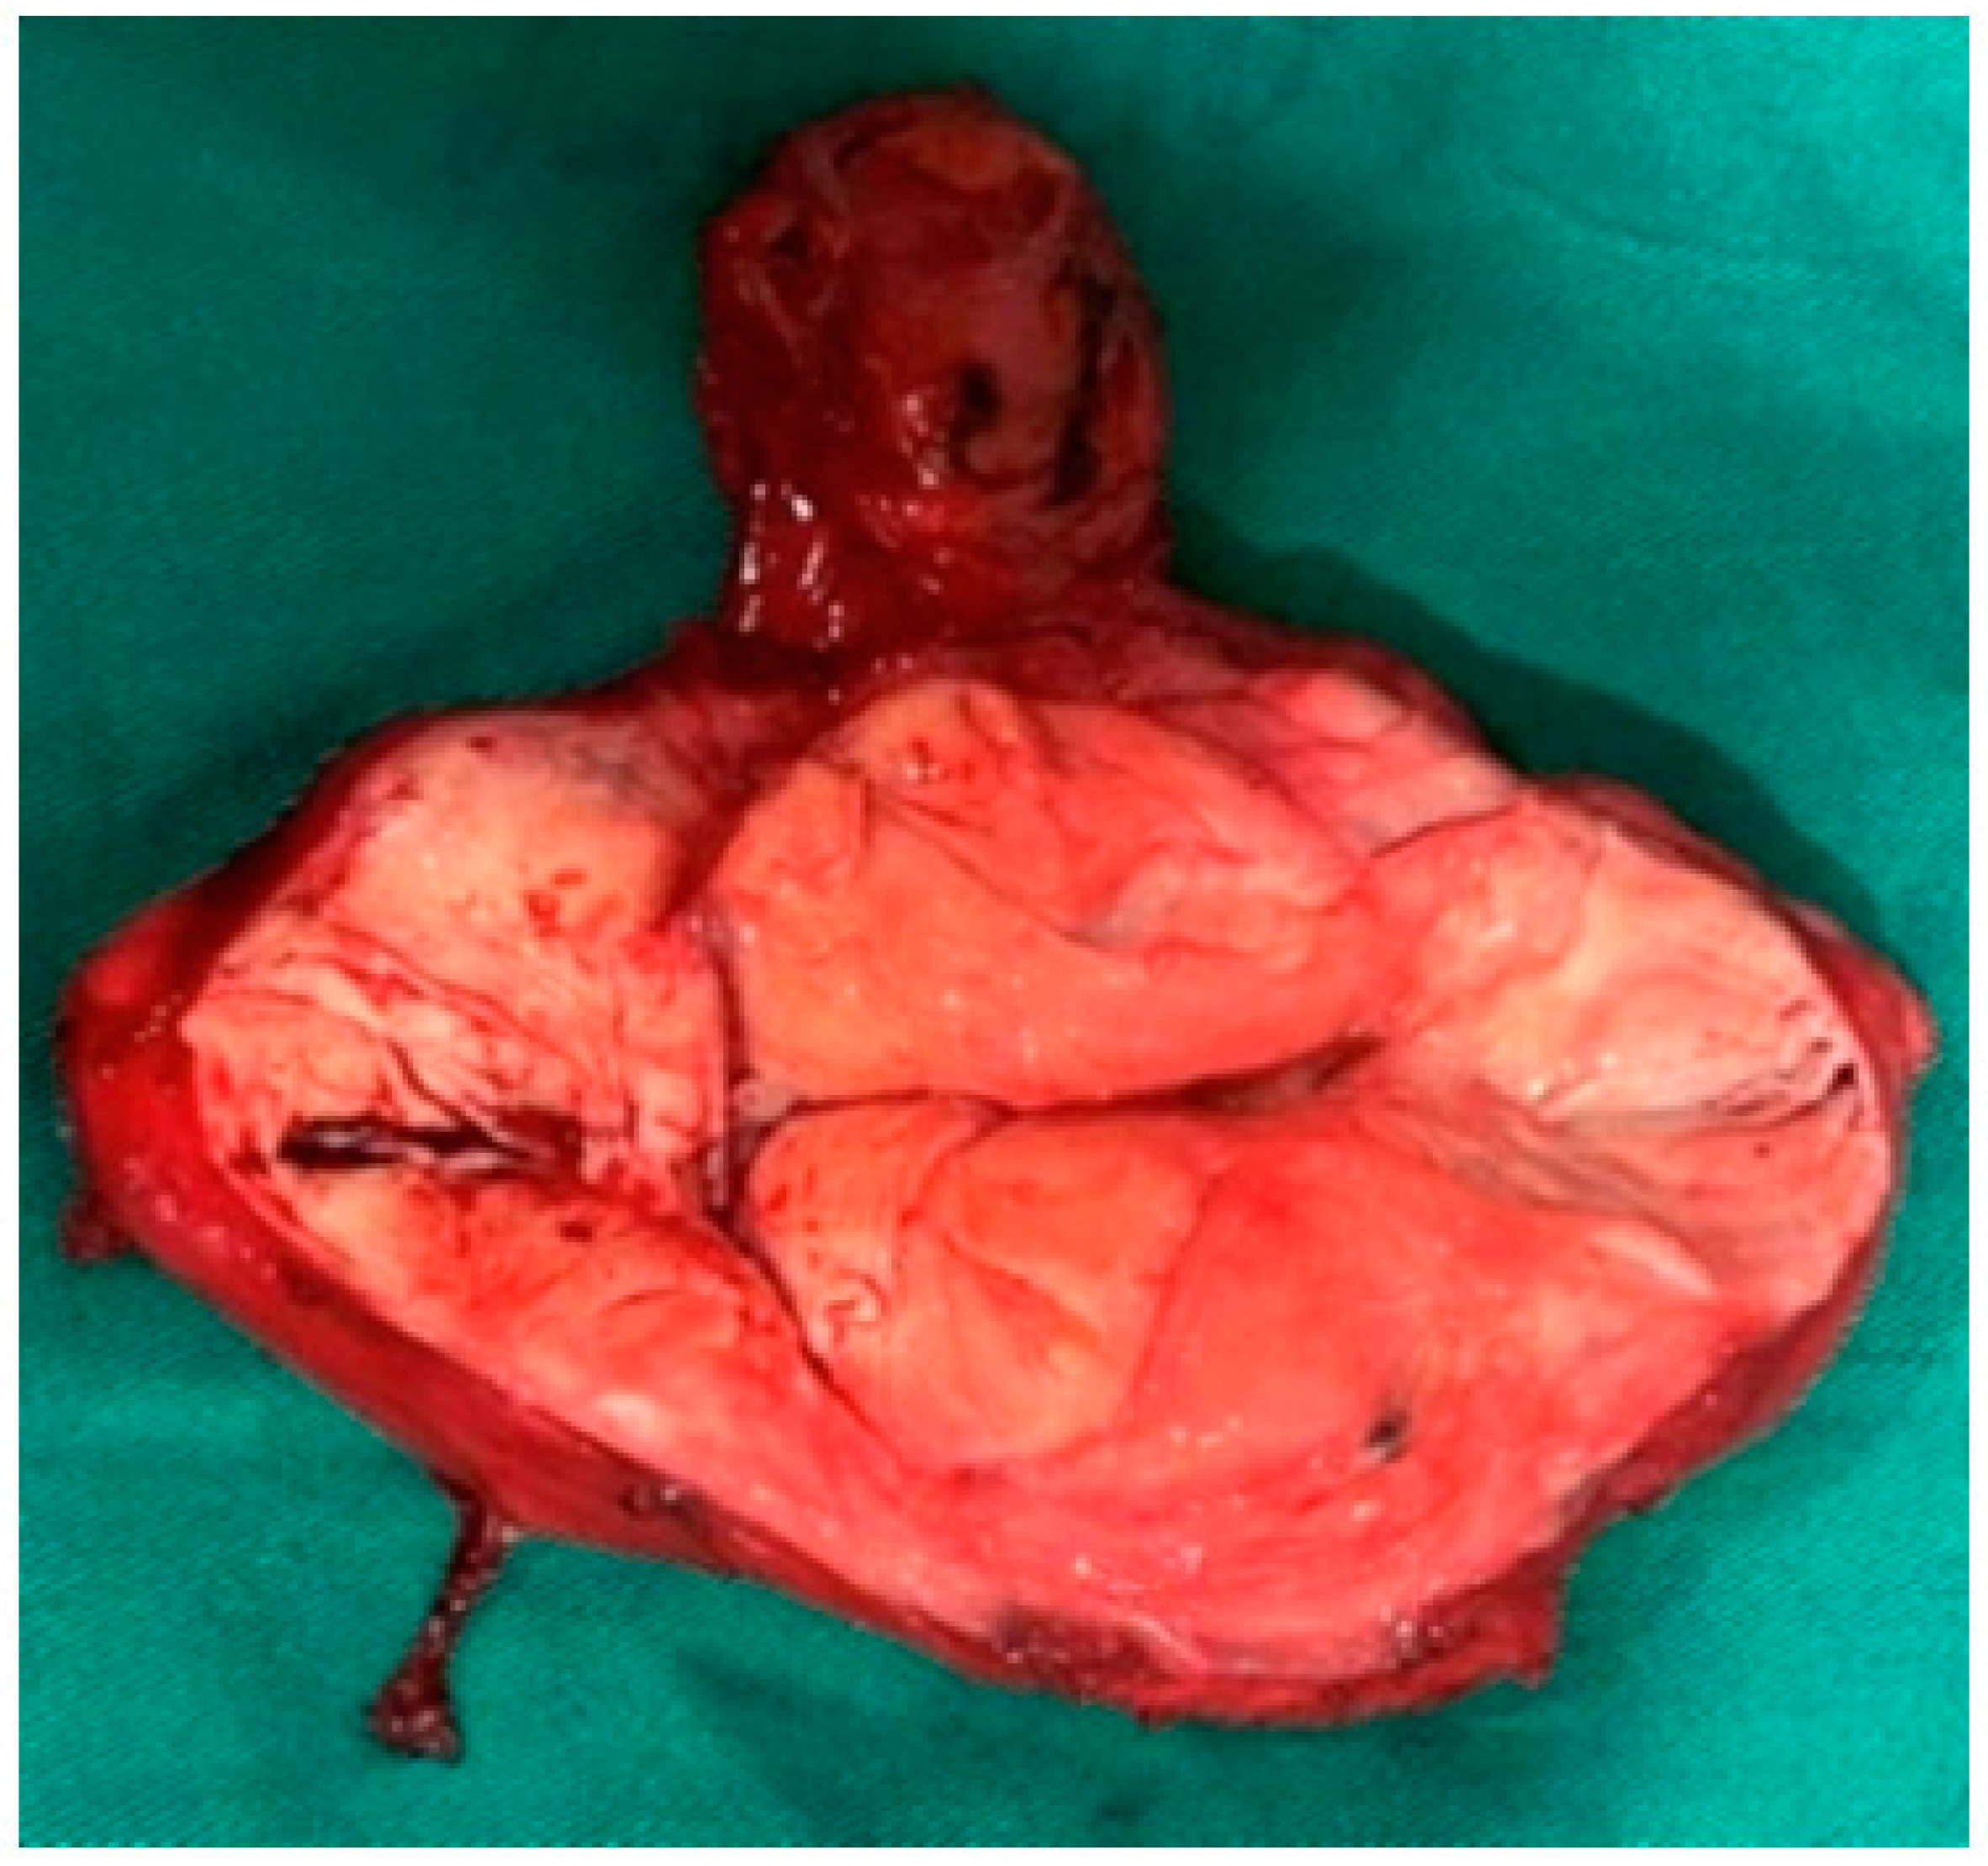

In Figure 5 we have demonstrated the macroscopic appearance of the lesion (Figure 5). The patient tolerated the manipulation well, without complications, and was discharged on the third postoperative day. We obtained the following histological result: “Non-encapsulated and locally infiltrative tumor formation, represented by monomorphic, relatively small-sized spindle-shaped or stellate cells with delicate chromatin, mostly hypocellular, with focal increased cellularity. Myxoid stroma with scattered delicate collagen fibers at periphery with accumulation of mature mast cells. Focal erythrocyte extravasates. Dilated capillaries and scattered large, thick-walled (with medial hypertrophy) or hyalinized vessels. Clustering of stromal smooth muscle bundles around vessels. Resection lines uninvolved”. Immunohistochemical result shows: “High expression of desmin and vimentin (100%). Positive ER expression. Lack of expression of the Ki-67 marker’.

Figure 5. Macroscopic appearance of the lesion.